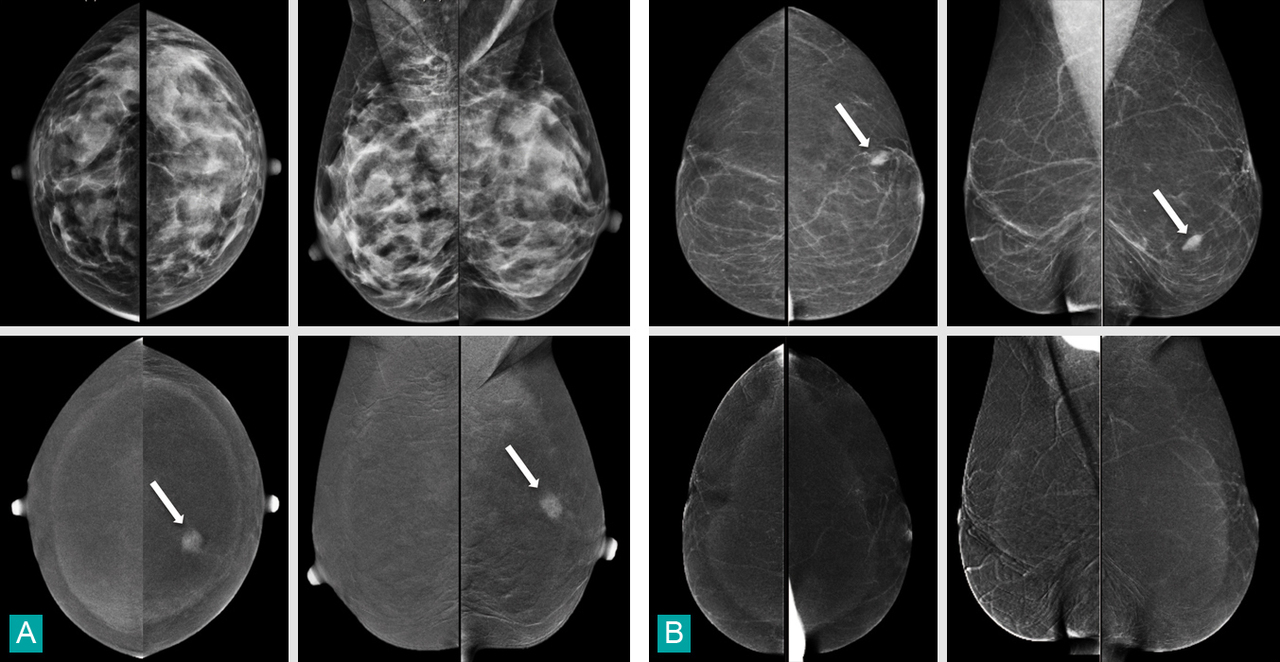

Mammographie : clichés du haut.Angiomammographie : clichés du bas.Chez la première patiente (fig. A), l'angiomammographie révèle la présence d'une masse rehaussée supéro-interne gauche (flèche), non décelable en mammographie en raison de l'hétérogénéité et de la densité glandulaire. L'échographie ciblée montre aisément une masse suspecte supéro-interne gauche qui, à la biopsie, révèle un carcinome canalaire infiltrant. Chez la secondepatiente (fig. 4B), l’angiomammographie permet de conclure que la masse dense ovalaire visible en mammographie dans le quadrant inféro-externe gauche (flèche) ne se rehausse pas, ce qui est en faveur de sa bénignité. La biopsie échoguidée conclut à une lésion de mastopathie fibreuse bénigne.